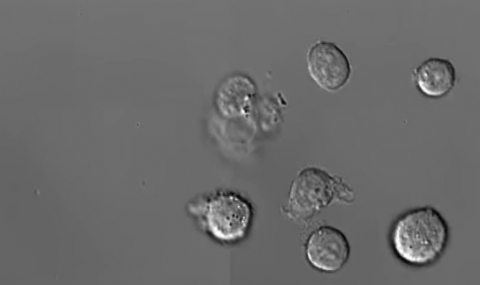

Австралийски учени са заснели за първи път в историята видео на смъртта на левкоцитите (белите кръвни клетки) в човешкия организъм, съобщи „Гардиън“.

Учените от университета в Мелбърн Ла Троуб са използвали микроскоп, който заснема по няколко хиляди изображения в секунда. Преди, учените вярваха, че смъртта и разпада на клетката е случаен процес. Видеото обаче показва високо ниво на планиране на клетъчна смърт. Биолозите са открили три етапа на този процес: подуване, експлозия и дезинтеграция.

„В началния етап на смъртта на клетката се образуват издатини. В един момент те се взривяват, при което се образуват клонки, подобни на огърлица. При взрива клетката се разпада на отделни перли. Околните клетки лесно абсорбират тези фрагменти. В перлите има определени молекули, които ако бъдат изядени от жива клетка, изпращат сигнал на други левкоцити, за това, че ги заплашва патогенен вирус.“, разказва Джорджия Аткинс Смит, която е съавтор на изследването.

Тези огърлици са наречени от учените „перловидни апоптоди“. Тяхната дължина е с 8 пъти по-дълга от тази на първоначалните клетки. За функциите им обаче учените все още не са достигнали до единодушие. Те могат да представляват механизъм за предупреждаването на съседни клетки за опасна инфекция, а в същото време и механизъм, който ускорява разпространението на патогенни бактерии и вируси в тялото.